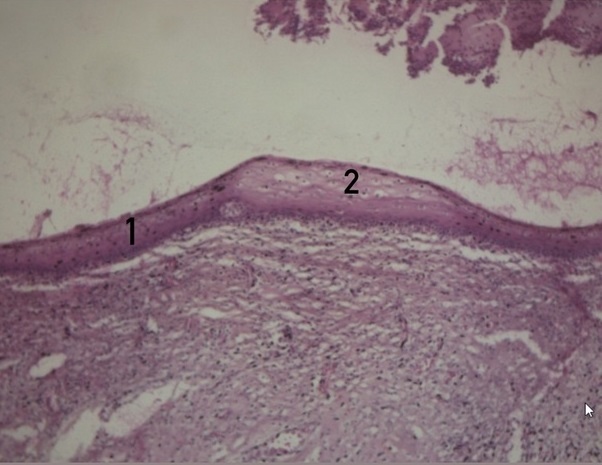

Рисунок 2 - Дисплазия эпителия слизистой оболочки шейки матки указана на рисунке цифрой 2

Примечание: окрашивание гематоксилином и эозином; увеличение х65

Рисунок 6 - Атрофия слизистой оболочки шейки матки (указана на рисунке цифрой 1) со склерозом сосудов (указан цифрой 2)

Примечание: окраска гематоксилином и эозином; увеличение х25